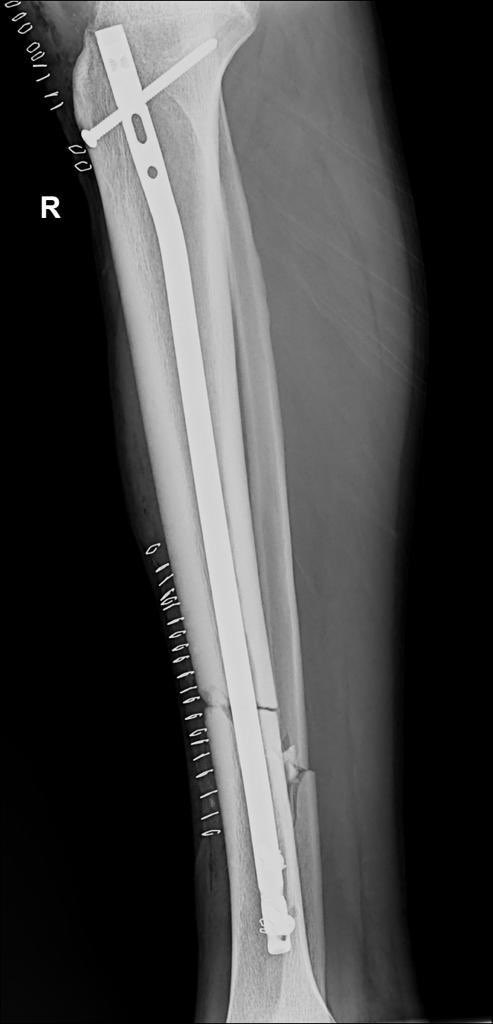

Nyuma y’imvune umunyezamu wa AS Kigali, Kimenyi Yves yagiriye ku mukino wa shampiyona wahuzaga Musanze Fc na AS Kigali, azamara amezi atandatu hanze y’ikibuga.

Kimenyi wabazwe kuwa mbere, arava mu bitaro by’Inkurunziza Orthopedic Specialized kuri uyu wa Kane tariki 2 Ugushyingo 2023.